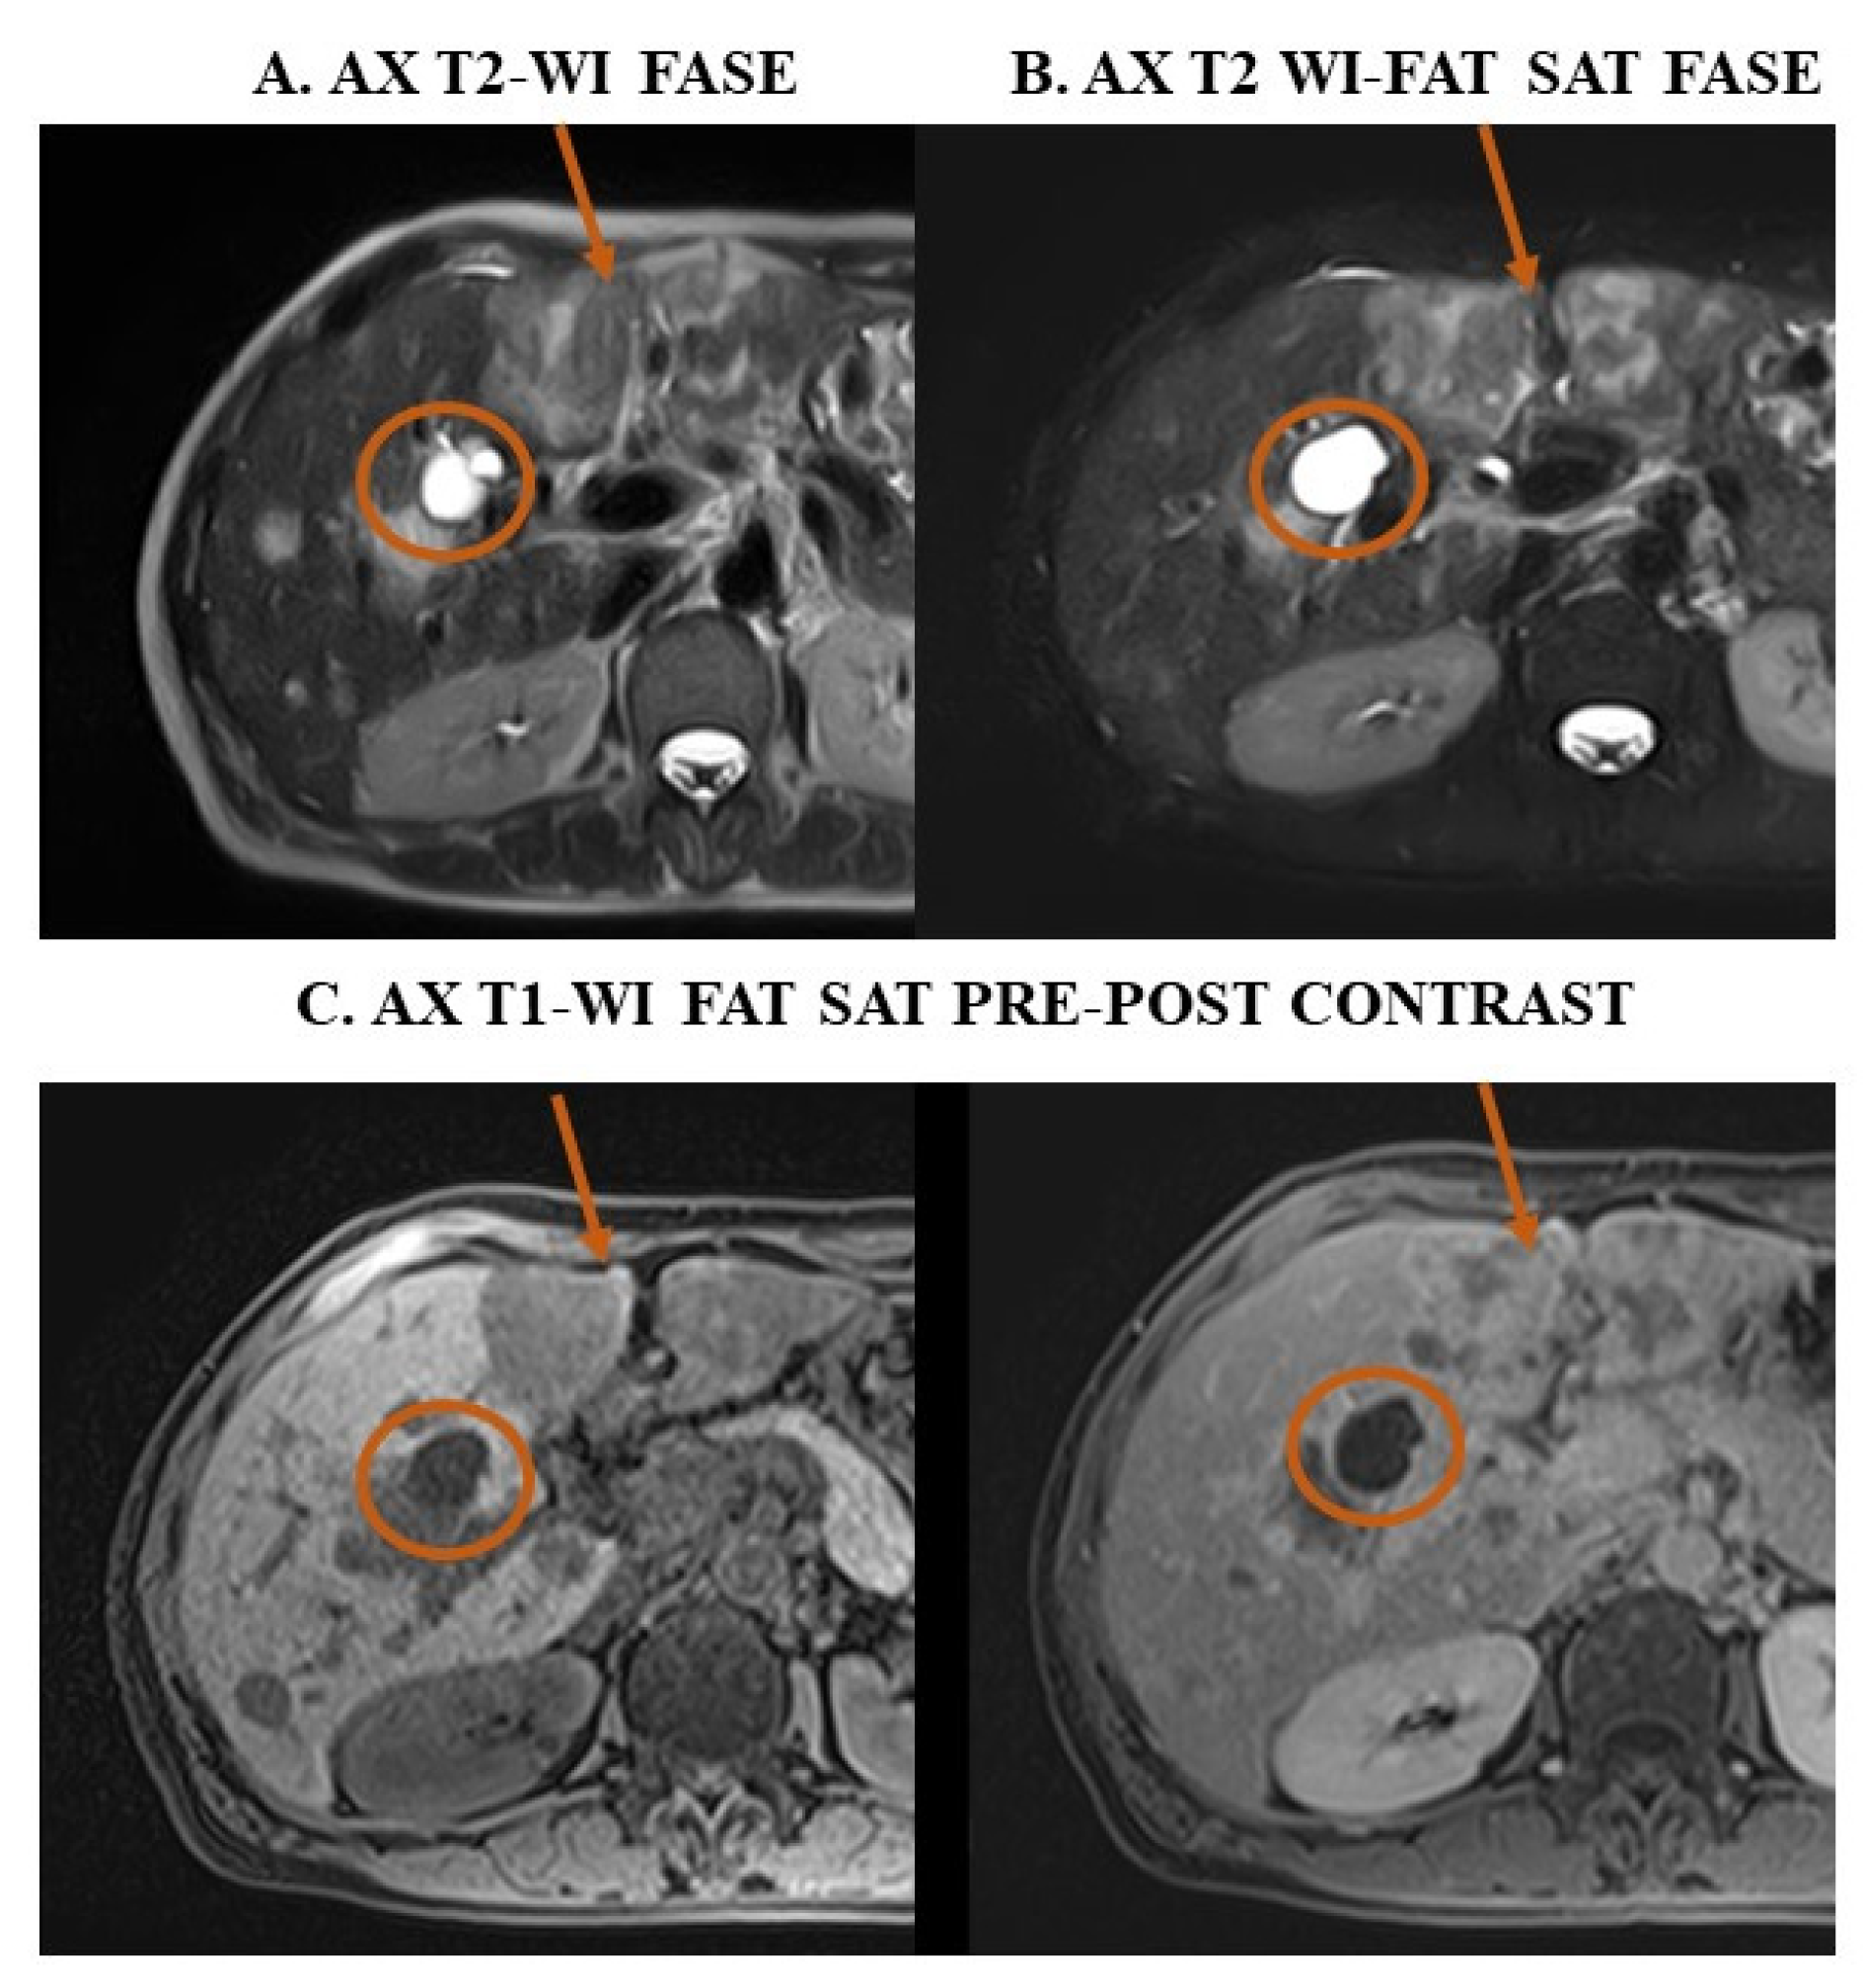

3. Examples of Applications of MRI Sequences in Upper Abdominal Analysis

4.3. Confirm Upper Abdomen Ultrasound Diagnosis Through MRI